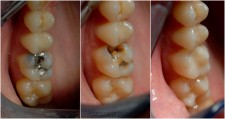

amalgamski ispun - karijes ispod starog amalgama - novi kompozitni ispun prije / poslije / poslije, bočni pogled stanje pri dolasku - nakon restauracije kompozitnim ispunom